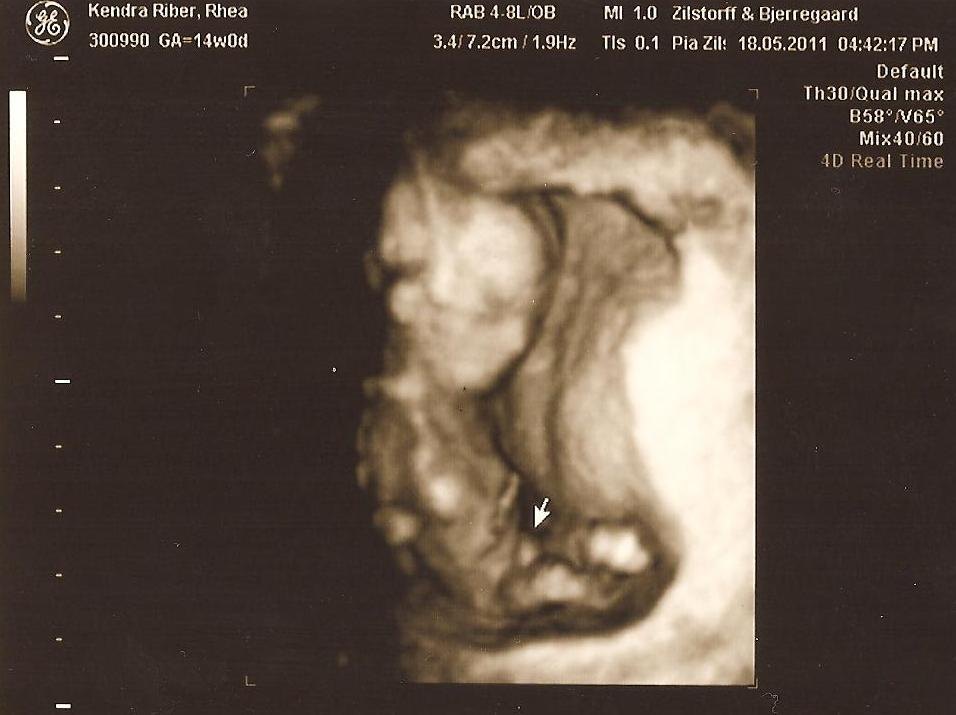

Og vi skal have en lille dreng :'). Er 14+0, og allerede nu var det så tydeligt at der gemmer sig en lille prins derinde. Er så overlykkelig, kan virkelig ikke beskrive det, og endda på vores årsdag, det godt nok den bedste årsdags gave man kunne ønske sig!